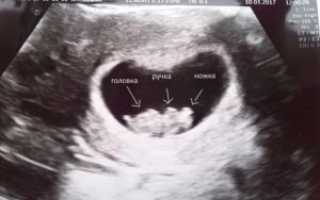

2. УЗИ.

Если при ультразвуковом исследовании диагностирована замершая беременность, видео «показывает» отсутствие сердцебиения у плода.

- Проведение УЗИ — диагностики, где на экране будет отсутствовать показатели сердцебиения плода.

Во время ультразвукового исследования врач может обнаружить замершую беременность. Этот метод считается «золотым» стандартом при диагностике данной патологии. Отсутствие сердцебиений и отставание плода в размерах – главные симптомы замершей беременности при УЗИ.